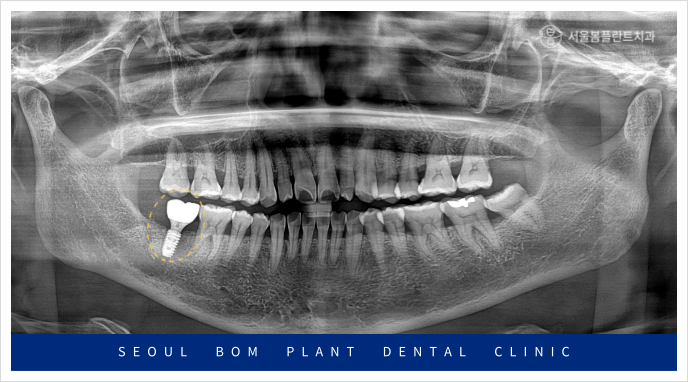

임플란트 식립을 위해 잇몸을 절개하여

내부를 확인해 보았더니,

뼈가 단단하게 자리 잡은 것을 확인할 수 있었습니다.

이로써, 충분히 안정적인 뼈 상태에서

임플란트를 식립할 수 있는

환경이 마련되었음을 알 수 있었습니다.

심한 염증으로 인해 발치 후 뼈이식을

진행했던 자리였기 때문에,

더 안정적인 임플란트 고정을 위해

신중하게 치료를 진행했습니다.